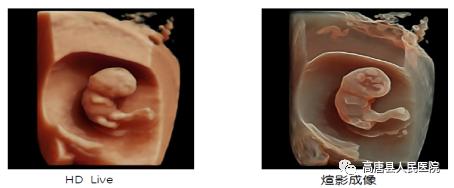

超越GE传统的HDlive成像模式,借助强大的GPU的处理能力,增加了组织透明度调节,实现100级可调,从内到外,一览无余。带来容积图像更强的边界感与距离感。煊影成像技术在早孕、双胎等评估有良好优势。

独有的煊影成像(HDlive Silhouette)和煊流技术(HDlive Flow),给容积超声带来出色的分辨率。胎儿识别追踪技术(SonoRenderlive)简化了胎儿表面成像,对于早孕的评估极有优势。